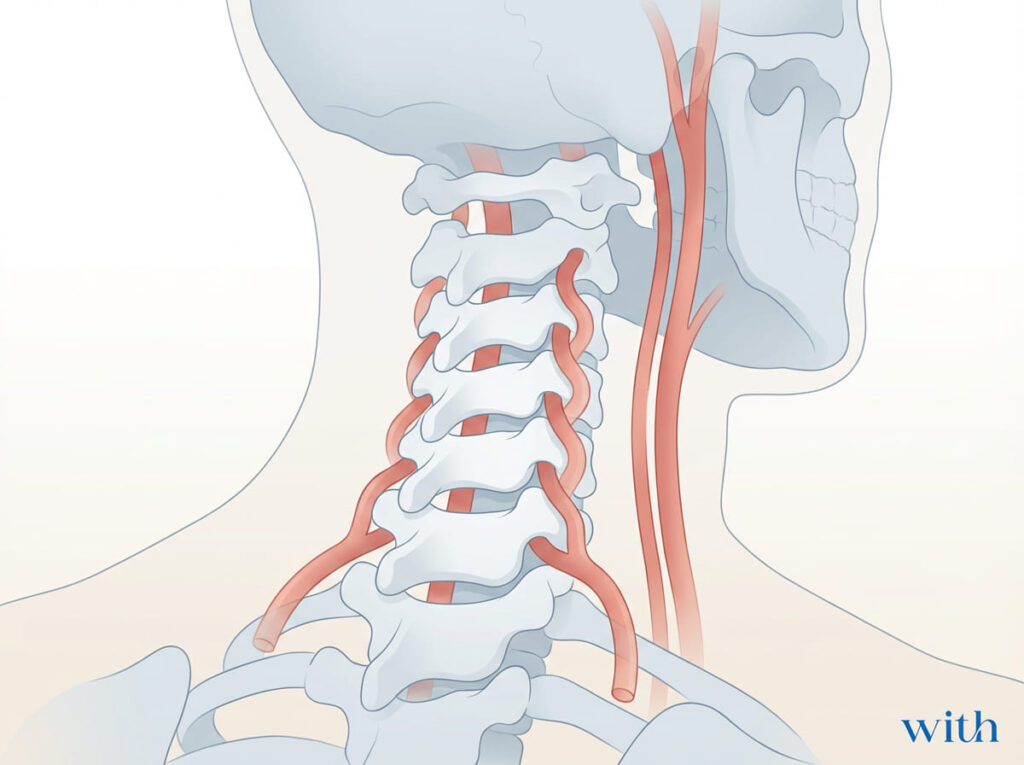

首を自分で鳴らすのは危険?強くひねるリスク

頸部への急速なスラスト(強いひねり)と

椎骨動脈解離・頸動脈解離との関連は、症例報告や疫学研究で示唆されています【論文②】【論文③】。

発生頻度は非常に低いと推定されていますが、因果関係の完全な証明は困難であり、医学的には「リスクが否定できない」と整理されています。

そのため、

- 勢いよくひねる

- 反復して習慣化する

行為は、安全側に倒す判断として推奨されません。

一方で、

頸部への急速スラストと血管解離との関連は

示唆されています【論文②】【論文③】。